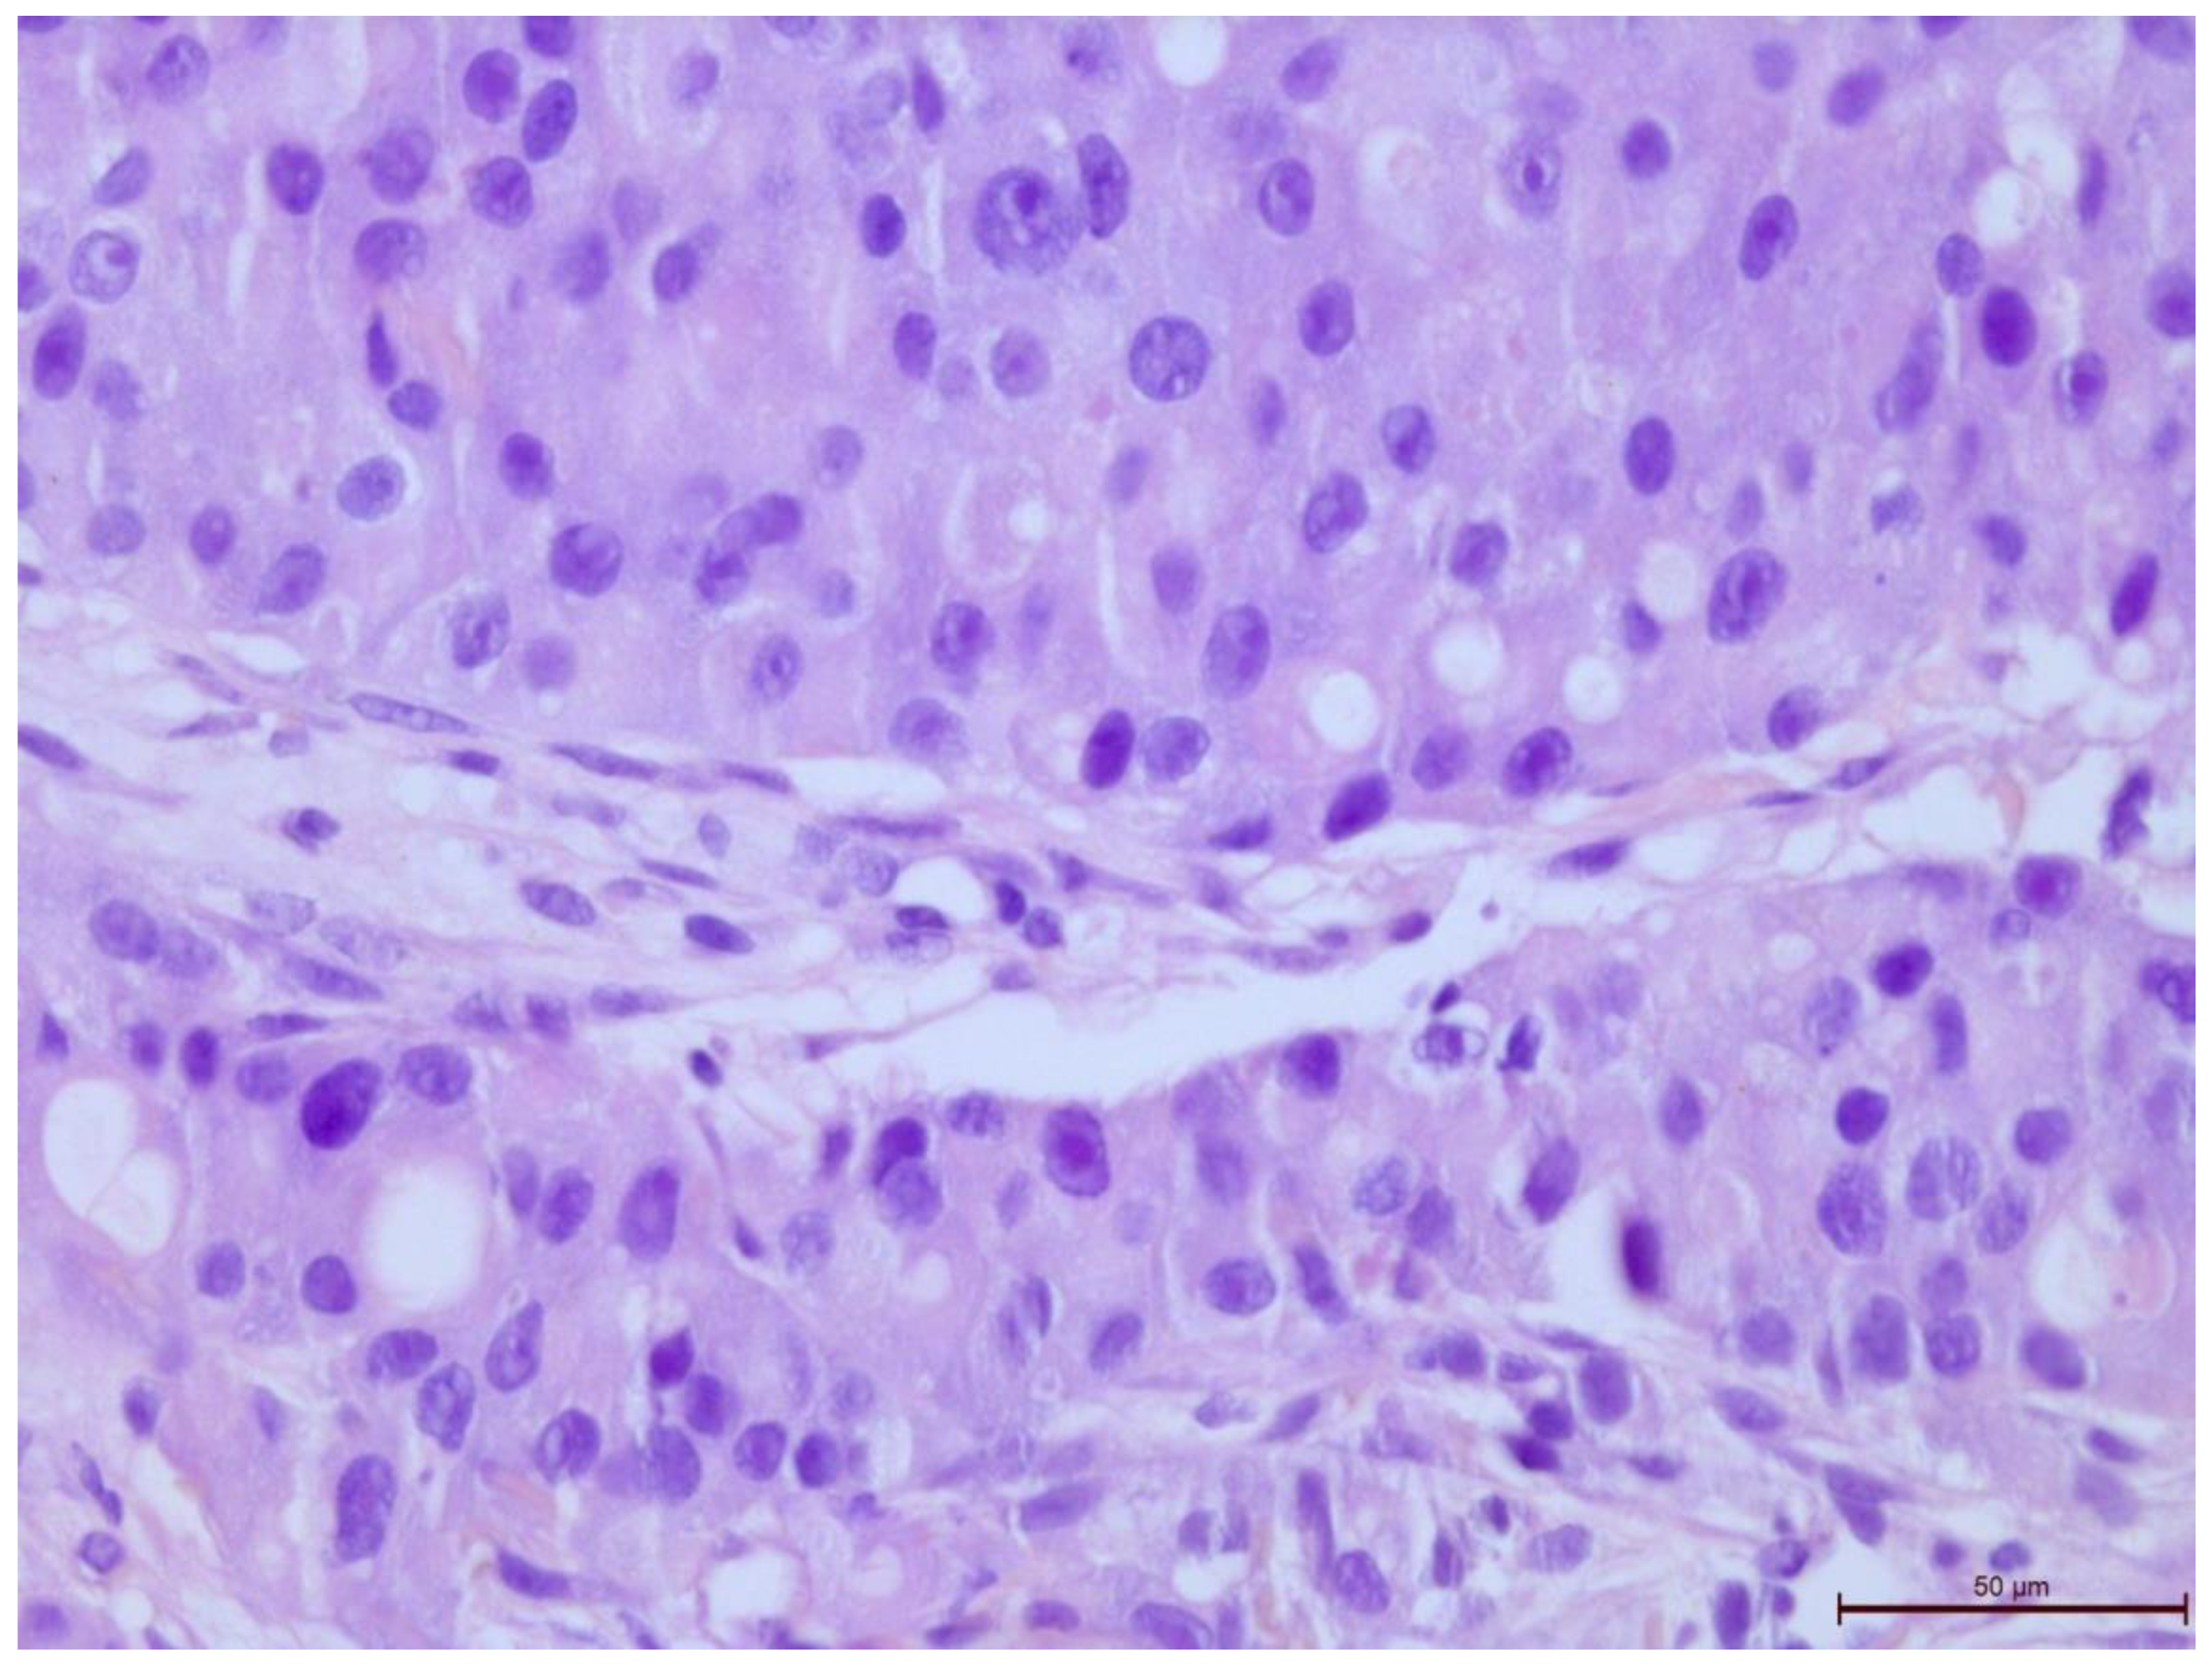

The T-lymphocyte infiltration in the tumor stroma was assessed according to the recommendations of the International Working Group on Immuno-Oncology of Breast Cancer Biomarkers (Figure 2, Figure 3, Figure 4, Figure 5, Figure 6 and Figure 7). The results are reported as the percentage of lymphocytes in the tumor stroma.

Figure 5. Invasive breast cancer with 5% T-lymphocyte infiltration in the tumor stroma, H&E staining, area 400×.

Preprints 109573 g005

Figure 6. Invasive breast cancer with 20% T-lymphocyte infiltration in the tumor stroma, H&E staining, area 400×.

Preprints 109573 g006